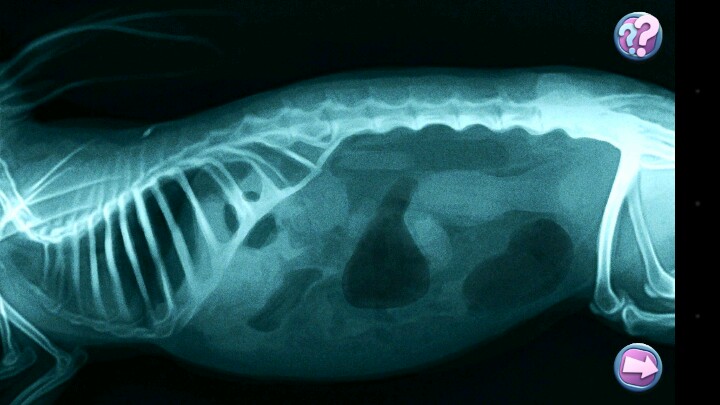

这个游戏最厉害的地方在于治疗动物的过程,简直真实到不行。

清除皮肤上的跳蚤和异物,检查耳朵,用听诊器检查内脏,剪爪子,点刺实验,血液检查,接种疫苗,检查发烧,清洁牙齿,照X光,超声检查。

每一项都有专门需要的器材,非常专业。